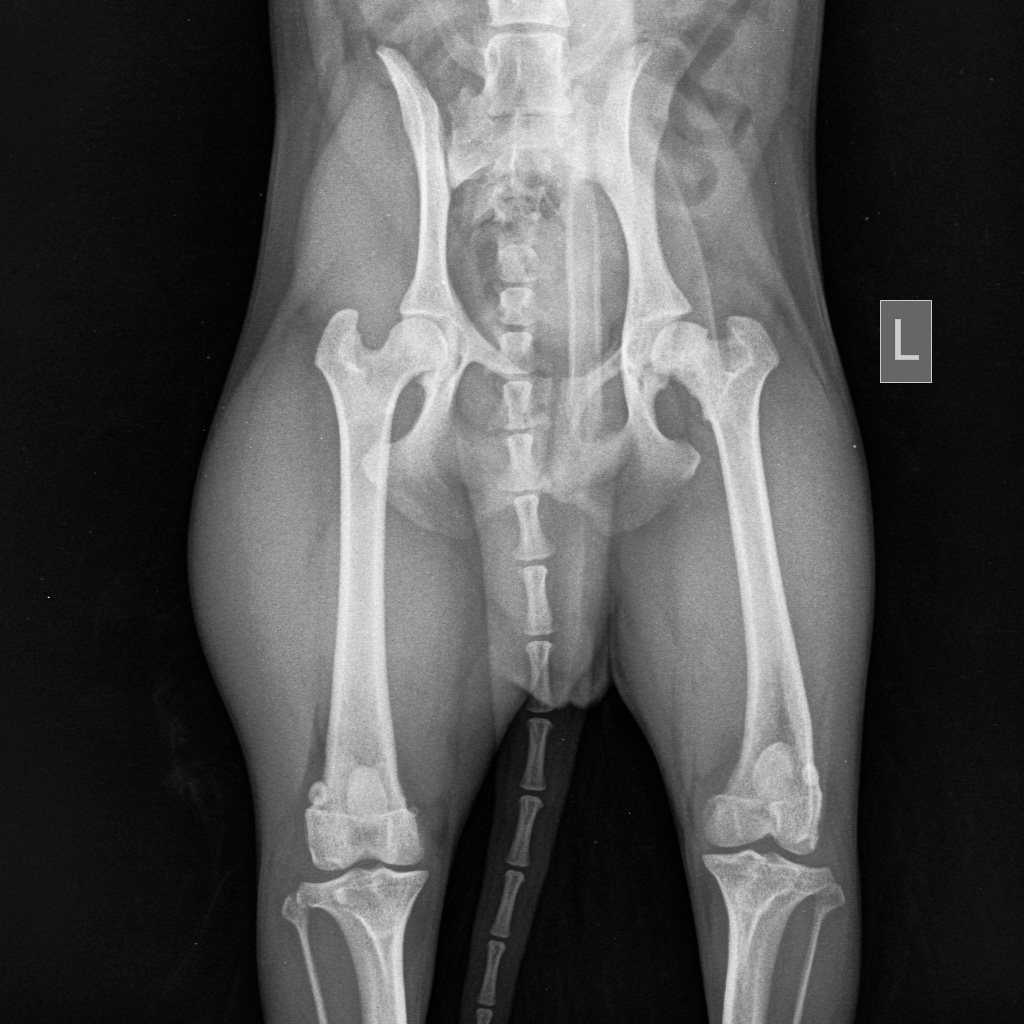

Как диагностировать асептический некроз головки бедра?

Диагностика болезни Пертеса у собак предполагает клиническое и инструментальное исследование.

Клинически оценивается вид хромоты у собак, мышечную массу области тазобедренного сустава, подвижность тазобедренного сустава.

Инструментальные методы включают в себя рентгенографию тазобедренного сустава, артроскопию, компьютерную томографию, УЗИ тазобедренного сустава.

Данные диагностические мероприятия позволяют точно поставить диагноз и дифференцировать от таких заболеваний как вывих надколенника, вывих тазобедренного сустава, дисплазия ТБС, инфекционные артриты, переломы головки и шейки бедра.